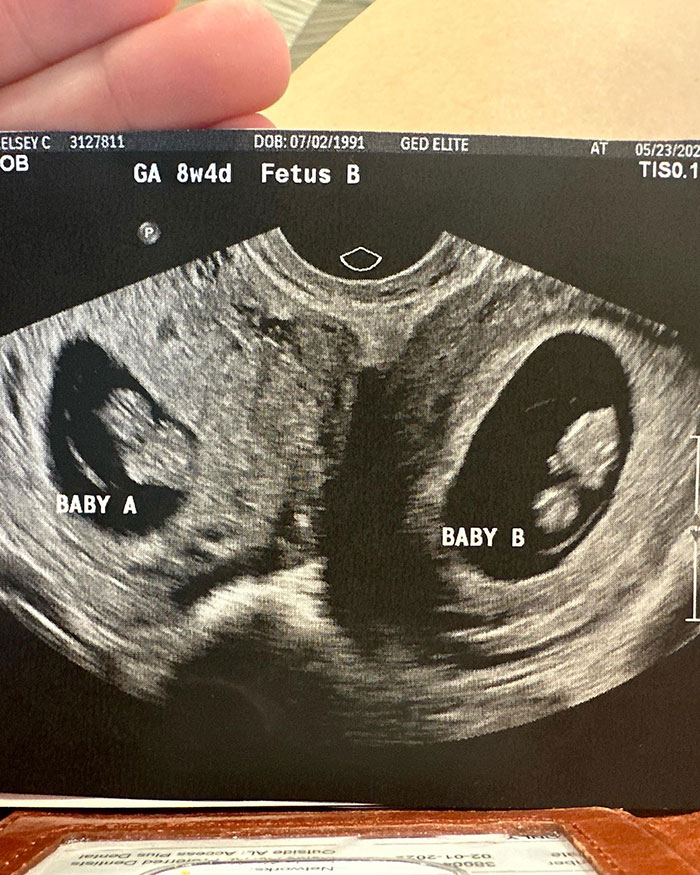

Kelsey Hatcher has a rare condition where she lives with a double uterus, expecting a child in each of the organs.

The expecting mom from Alabama, USA, was in fact born with two functional uteri that each have their own cervix.

Upon discovering her pregnancy last spring, followed by a first ultrasound, Kelsey shared the amazing news that she was not only pregnant but expecting babies in both organs, with her husband Caleb.

Dr. Richard Davis, a specialist in high-risk pregnancies at the University of Alabama, told the news outlet: “A double cervix or double uterus is way under 1%, maybe three per 1,000 women might have that.

“And then the probability of you having a twin in each horn is really crazy.”